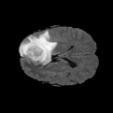

To better retain the deep features of an image and solve the sparsity problem of the end-to-end segmentation model, we propose a new deep convolutional network model for medical image pixel segmentation, called MC-Net. The core of this network model consists of four parts, namely, an encoder network, a multiple max-pooling integration module, a cross multiscale deconvolution decoder network and a pixel-level classification layer. In the network structure of the encoder, we use multiscale convolution instead of the traditional single-channel convolution. The multiple max-pooling integration module first integrates the output features of each submodule of the encoder network and reduces the number of parameters by convolution using a kernel size of 1. At the same time, each max-pooling layer (the pooling size of each layer is different) is spliced after each convolution to achieve the translation invariance of the feature maps of each submodule. We use the output feature maps from the multiple max-pooling integration module as the input of the decoder network; the multiscale convolution of each submodule in the decoder network is cross-fused with the feature maps generated by the corresponding multiscale convolution in the encoder network. Using the above feature map processing methods solves the sparsity problem after the max-pooling layer-generating matrix and enhances the robustness of the classification. We compare our proposed model with the well-known Fully Convolutional Networks for Semantic Segmentation (FCNs), DecovNet, PSPNet, U-net, SgeNet and other state-of-the-art segmentation networks such as HyperDenseNet, MS-Dual, Espnetv2, Denseaspp using one binary Kaggle 2018 data science bowl dataset and two multiclass dataset and obtain encouraging experimental results.